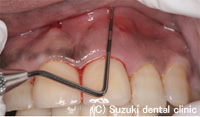

| 歯茎の状態をチェックするポケット短針にて診査 |

歯と歯ぐきの際(歯周ポケット)に挿入

⇒ ポケットの深さ14mm(正常値2mm) |